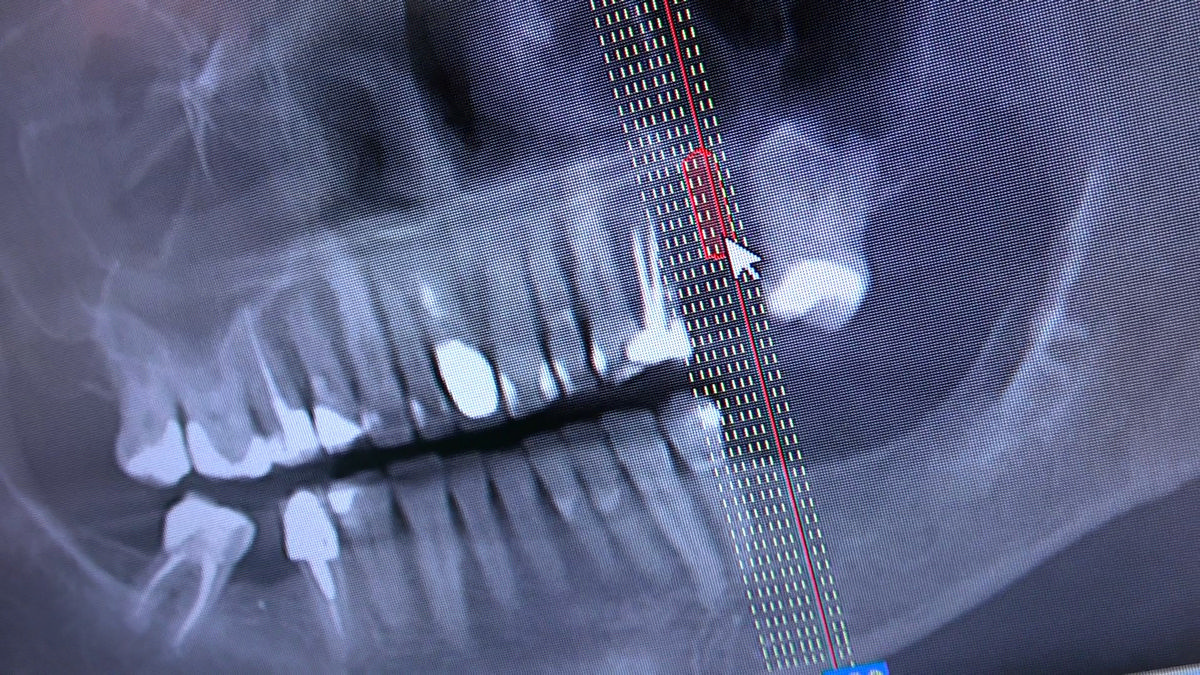

PRACTICULUM IMPLANTOLOGII - SEZON X - SESJA 4 - GRUPA B